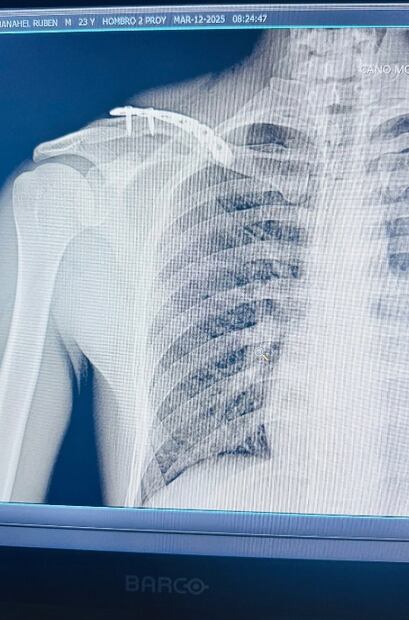

A través de su cuenta de Instagram, la voz detrás de “Madonna” compartió fotos de las acrobacias que realizó en el aire. En la descripción, añadió: “Clavícula salió del chat”, junto con emoticones de caritas riendo. También publicó las radiografías de la fractura en su clavícula.

Según explicó su doctor, al artista le fueron colocados cinco clavos de titanio en el hueso afectado. “Para que no se oxide el muchachón”, bromeó el famoso.